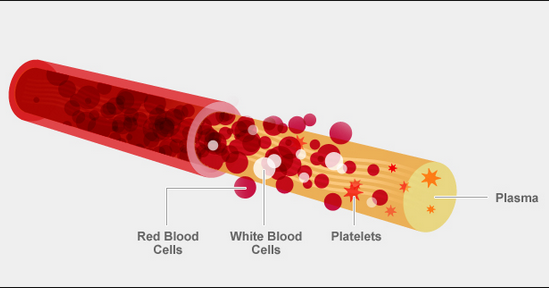

Lord Byron ….. blood software package ……

Why Is AB Blood Type So Rare? It’s All About The Red Blood Cells

Mar 25, 2016 – “Blood group A has only A antigens.” Similarly, blood group B has only B antigens, blood group AB has both, and blood group O has neither A nor B antigens on the surface of the red blood cells. These four groups are the most important because they indicate which blood type a patient can safely receive in a transfusion.

AB Positive Blood Type Facts

about Lord Byron arteries OUTPUT messages|

Thrombocytes

AB Positive Blood Type Facts (AB+). 1. Universal Plasma Donor and Universal Red Cell Recipient. The nature of antigens present in the serum determines the …

Blood type – Wikipedia

A blood type is a classification of blood based on the presence and absence of antibodies and …. Therefore, an individual with type AB blood can receive blood from any group (with AB being preferable), but cannot donate blood to any group …

Heme | definition of heme by Medical dictionary

Heme binds and carries oxygen in the red blood cells, releasing it to tissues. Also spelled haeme. See also hemoglobin, porphobilinogen, protoporphyrin.

Heme | definition of heme

Heme | definition of heme OUTPUT formats

Heme | definition of Theme …. SCheme